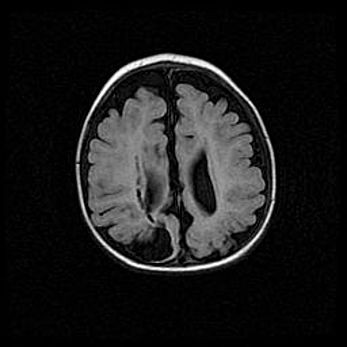

Множественные кисты обоих полушарий головного мозга, наибольшая из них в правой затылочной области. Ассиметричная атрофическая гидроцефалия.

Возраст: 7 месяцев

Вес: 5660 г

Пол: мужской

Окружность головы: 41,5 см

Срок гестации: 28-29 недель

Кисты головного мозга развиваются в результате многоочаговых некрозов вещества мозга и возникают вследствие перенесенной перинатальной инфекции, менингитов, энцефалитов, асфиксии, родовой травмы, расстройств мозгового кровообращения различного генеза. Образованию кист в веществе головного мозга плодов и новорожденных способствуют такие факторы, как высокое содержание в нем воды, недостаточная (или отсутствие) миелинизация и слабая астроглиальная реакция на повреждение.

Кисты могут сочетаться с гидроцефалией и другими поражениями головного мозга.